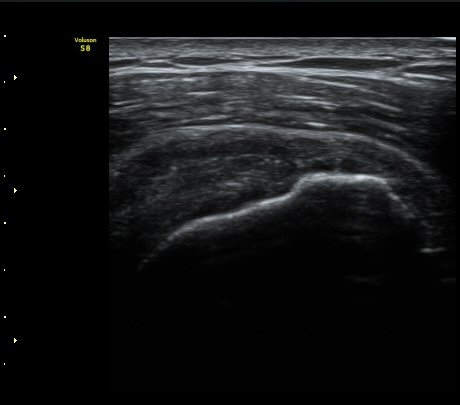

À̵ιڱ٠Ⱦ´Ü¸é°Ë»ç¿¡¼­ Á¤¸Æ³¶ÀÇ ºÎÁ¾ÀÌ °üÂûµÊ(±×¸² 1).